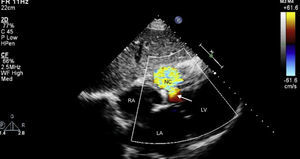

Although the patch significantly reduced the interventricular communication, a residual defect remained, with turbulent left-to-right shunt, draining into a cavity that corresponded to the aneurysmal dissection of the septum, and that communicated distally with the right ventricle (Figure 2), findings confirmed by cardiac magnetic resonance imaging (Figures 3 and 4).

Transthoracic echocardiography, subcostal view. After surgery, an interventricular communication remains, with left-to-right shunt. LA: left atrium; LV: left ventricle; NC: neocavity formed by the dissection of the interventricular septum; RA: right atrium. Arrow: interventricular septal rupture.